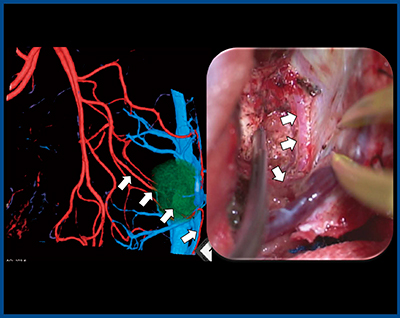

症例3は,59歳,女性,左前頭葉膠芽腫である。腫瘍に向かう太い血管がfeederと考えられたが,詳細に観察すると,腫瘍の後方に通過する血管も確認でき,腫瘍後方を栄養する動脈もあると推測された(図4)。

そのため手術では,腫瘍内部に入る血管は凝固切離して出血を抑え,正常灌流の可能性がある血管は腫瘍後方まで走行していることが確認されたため,腫瘍から剥離して温存した。腫瘍後方は運動領域であり,血管を残すことで脳梗塞を防ぎ,麻痺を生じることなく脳腫瘍を摘出することができた。

図4 症例3:左前頭葉膠芽腫の術前3D-CTA